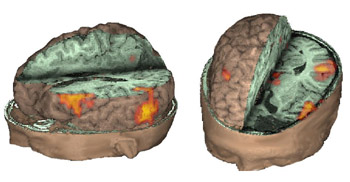

3D Rendering + Orthogonal View

Surface rendering and orthogonal views can be combined in one procedure. This allows us to see activation (or lesions) of the cortex and deep structures of the brain. The bleeding through of activation is obviated. External landmarks of the head and face may also help in surgical navigation.

Surface and orthogonal rendering of the brain is viewed in natural anatomical orientation. This means that the structures appear as if they were under direct sight. For that reason the left hemisphere appears on the right side of the left-top-rostral view, and on the left side on the left-top-posterior view. The fMR image presented here depicts activation of the angular gyrus observed in a right-left laterality decision task. The hemi-axial plane shows the activation placed in the deep portion of the left parietal sulcus.

Case 1

11-year-old right handed boy with intractable epilepsy and left hemiparesis. Patient was mapped for language as part of his work up for epilepsy surgery with a "Semantic Fluency Task."

3D-surface rendering and orthogonal views. The images show activation of Broca's area along pars orbitales, triangularis and opercularis in the left hemisphere. Activation is also observed in visual areas likely related to visual strategies. Activation of the basal ganglia is occasionally seen as in this case. Activation can be localized on one image including the cortex, the sylvian fissure, the calcarine fissure, the lateral ventricles and along the midline.